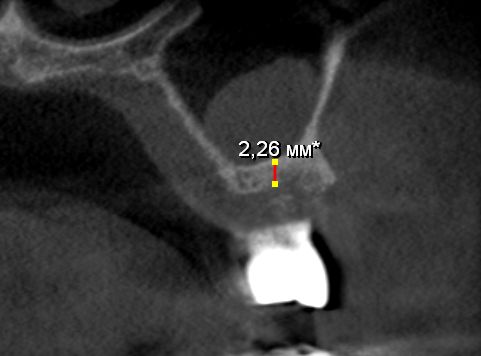

Пациент обратился с целью протезирования. На компьютерной томографии выявлен недостаток костной ткани по высоте (3−5 мм) за счет углубления гайморовой пазухи. Следующим этапом в области отсутствующих зубов 1.5, 1.6 и 1.7 планируется дентальная имплантация.

Врачом А.Г. Геворкяном выполнена операция по наращиванию костной ткани (открытый синуслифтинг). На контрольном снимке определяется увеличение объема костной ткани по высоте.